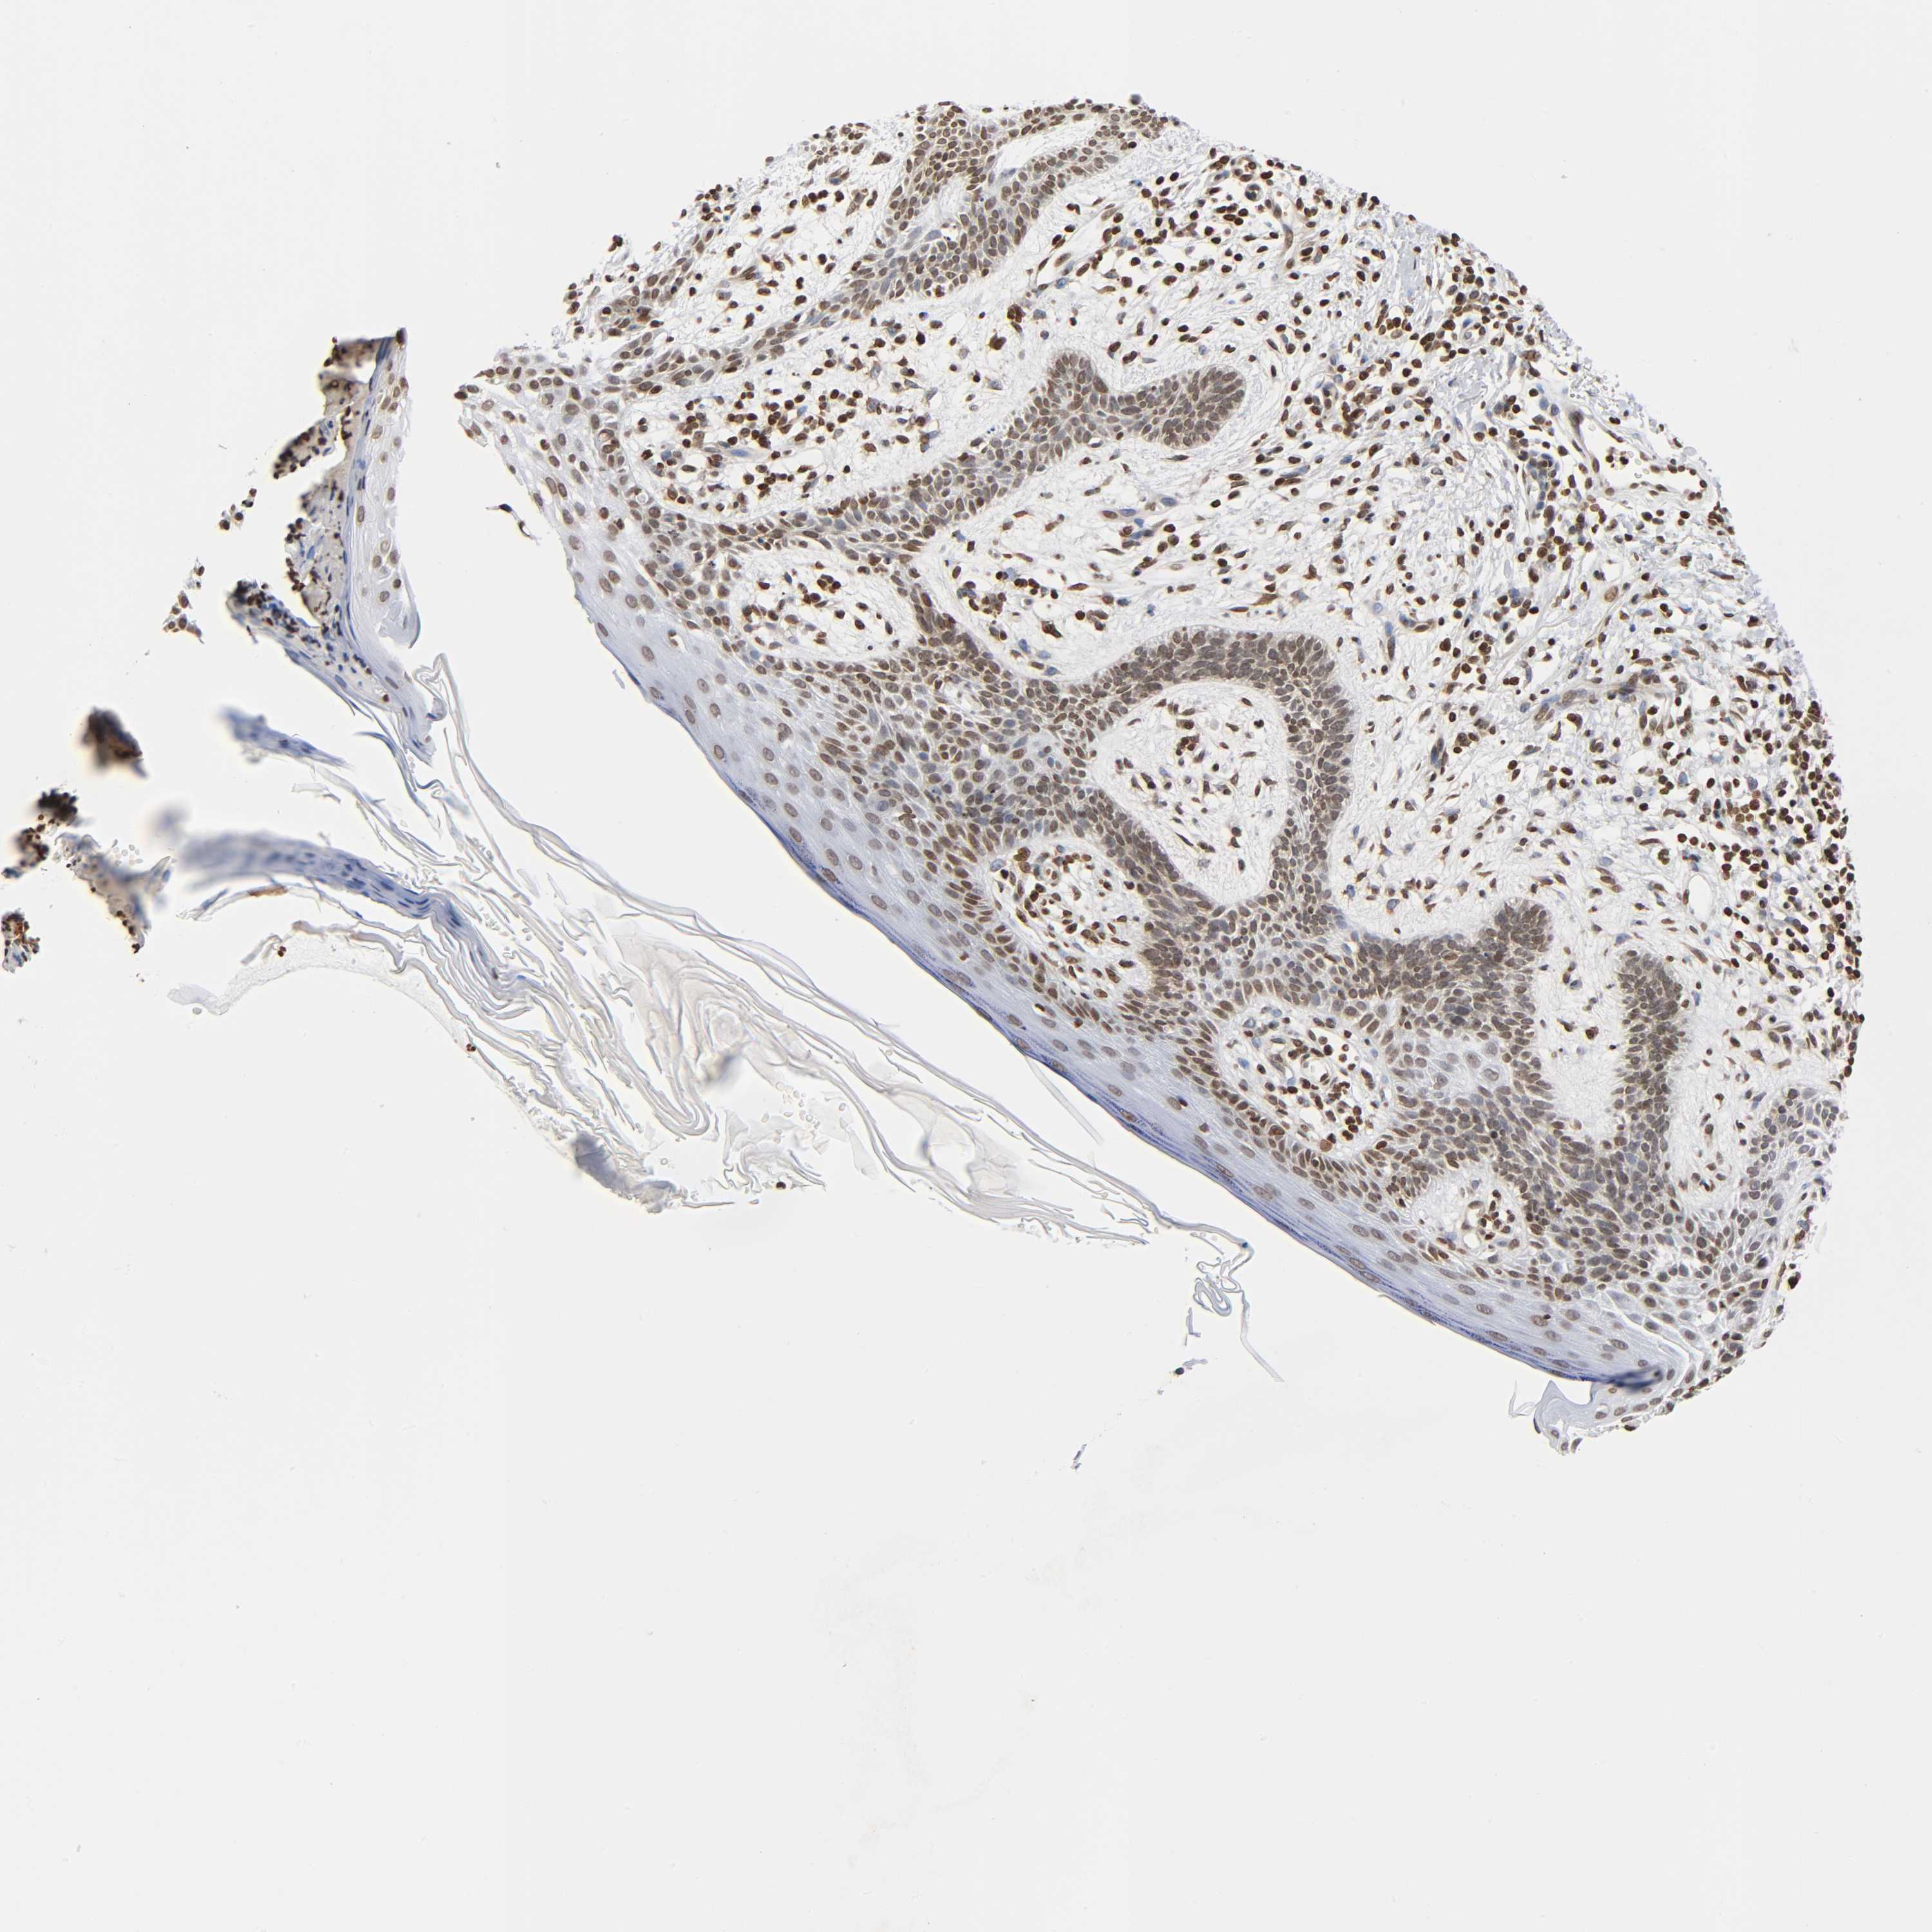

Basal cell and squamous cell cancer

SKIN CANCER - Protein expressioni

A mouse-over function shows sample information and annotation data. Click on an image to view it in a full screen mode. Samples can be filtered based on level of antibody staining by selecting one or several of the following categories: high, medium, low and not detected. The assay and annotation is described here.

Each image is clickable and will lead to virtual microscopy that enables deeper exploration of all samples and also displays staining intensity scores, fraction scores and subcellular localization as well as patient and tissue information for each sample.

Antibody HPA004203

Staining

High

Intensity

Strong

Quantity

>75%

Location

Nuclear

Squamous cell carcinoma, NOS

Basal cell carcinoma